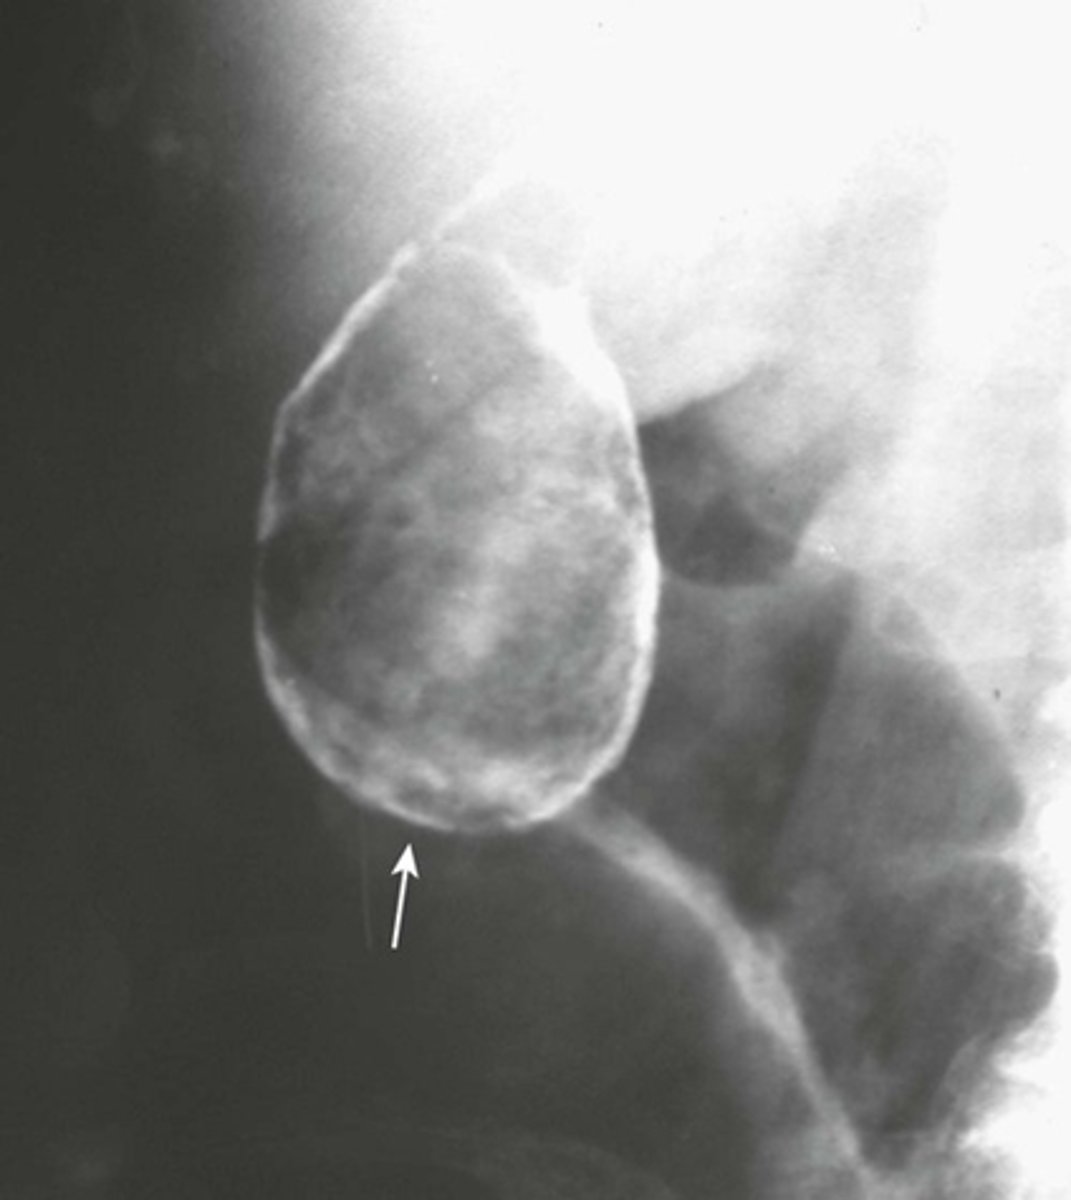

Pneumatosis cystoides intestinalis.

SOLID WHITE ARROWS:

Clusters of air-containing CYSTs associated with the left colon.